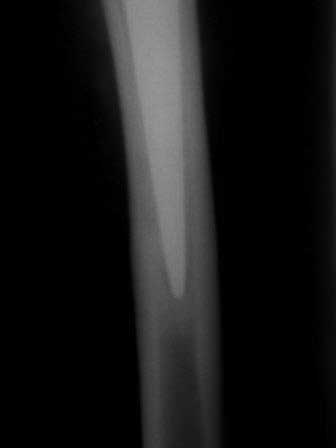

В дополнение к моему вышеуказанному пациенту. Досылаю послеоперационный снимок, который я не выслал сразу.

Расшорошили вертлужную впадину (дебридмент) Заменили чашку,учитывая невозможность полностью исключить инфекционный генез нестабильности, установили вертлужный компонент цементной фиксации (цемент с ванкомицином), поменяли головку из-за изменившихся взаимоотношении между бедренным компонентом и новой чашкой. Рану зашили наглухо. Провели антибактериальную терапию Кубицином. Выписали на 10 сутки после операции. Болевой синдром купирован, пациент радостный, уехал к себе в Калугу. Приедет на контрольный осмотр через месяц.

На заключительных снимках явная нестабильность чашки и вероятная ножки, возможно на повторный прием придет не столь радостный (пессимистический прогноз) надеюсь, что все будет по-другому

Нет вы не поняли! Вы поспешили с выводом! Я не смог выслать окончательный, послеоперационный снимок, по техническим причинам. Я это сделал позже, что Вы и видите ниже! Извините, если я Вас запутал!

С последним, третьим снимком он ко мне и обратился, после чего он был и прооперирован на правом тазобедренном суставе!